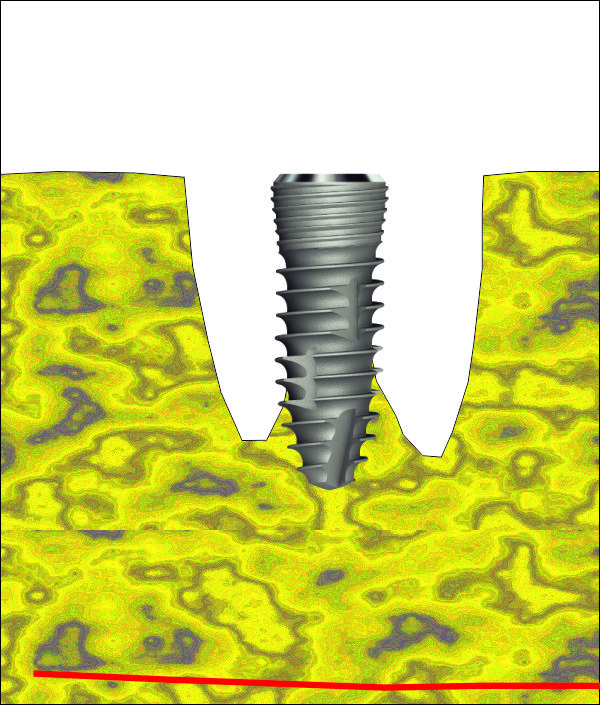

Схема на имедиатно поставен зъбен имплант от серията IS1 на производителя Neobiotech.

Вижда се как формата на импланта наподобява формата на зъбния корен - съответно

на зъбната алвеола след екстракцията на зъба при еднокоренови зъби. При

многокоренови зъби разширението на имплантатната шийка също е от полза по

отношение на имедиатното поставяне, но е необходимо да се използва доста

по-широк зъбен имплант - поне два пъти по-широк от диаметъра на корена, тъй като

долните молари са с по два корена, а при горните има също два във всяка една

равнина. Обикновено при горните молари палатиналният корен е доста по-голям

диаметър от останалите и поради това доста зъболекари препоръчват именно на

неговото място да се поставя зъбен имплант при имедиатно имплантиране. Нашият

екип не препоръчва подобен подход - в действителност диаметърът на корена е

доста голям, но при поставяне на импланта на неговото място протетичният

резултат впоследствие не е добър. Необходимо е да се изработи корона с много

голям екватор с всички негативни последици от това - трудно почистване и

опасност от постоянно разциментиране.